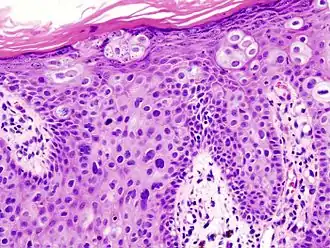

Histopathologically, the epidermis in SCC in situ (Bowen’s disease) will show hyperkeratosis and parakeratosis. There will also be marked acanthosis with elongation and thickening of the rete ridges. These changes will overly keratinocytic cells which are often highly atypical and may in fact have a more unusual appearance than invasive SCC. The atypia spans the full thickness of the epidermis, with the keratinocytes demonstrating intense mitotic activity, pleomorphism, and greatly enlarged nuclei. They will also show a loss of maturity and polarity, giving the epidermis a disordered or “windblown” appearance.

Two types of multinucleated cells may be seen: the first will present as a multinucleated giant cell, and the second will appear as a dyskeratotic cell engulfed in the cytoplasm of a keratinocyte. Occasionally, cells of the upper epidermis will undergo vacuolization, demonstrating an abundant and strongly eosinophilic cytoplasm. There may be a mild to moderate lymphohistiocytic infiltrate detected in the upper dermis.[33]

Squamous cell carcinoma in situ, showing prominent dyskeratosis and aberrant mitoses at all levels of the epidermis, along with marked parakeratosis.[33]